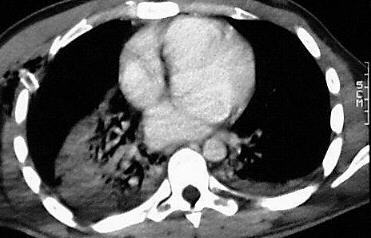

Perikarderguss

Akut auftretende perikardiale Flüssigkeitsansammlungen können ab ca. 250 ml zu einer Herzbeuteltamponade führen. Als Ursachen dafür kommen beispielsweise Aortendissektionen, perforierende Traumen, Urämie sowie bakterielle, virale und rheumatoide Perikardentzündungen in Frage. Computertomographisch lässt sich ein zirkulärer, dem subepikardialen Fettgewebe anliegender hypodenser Saum darstellen. Bei einer zugrunde liegenden Perikarditis können verdickte, kontrastmittelaufnehmende Perikardblätter nachweisbar sein.